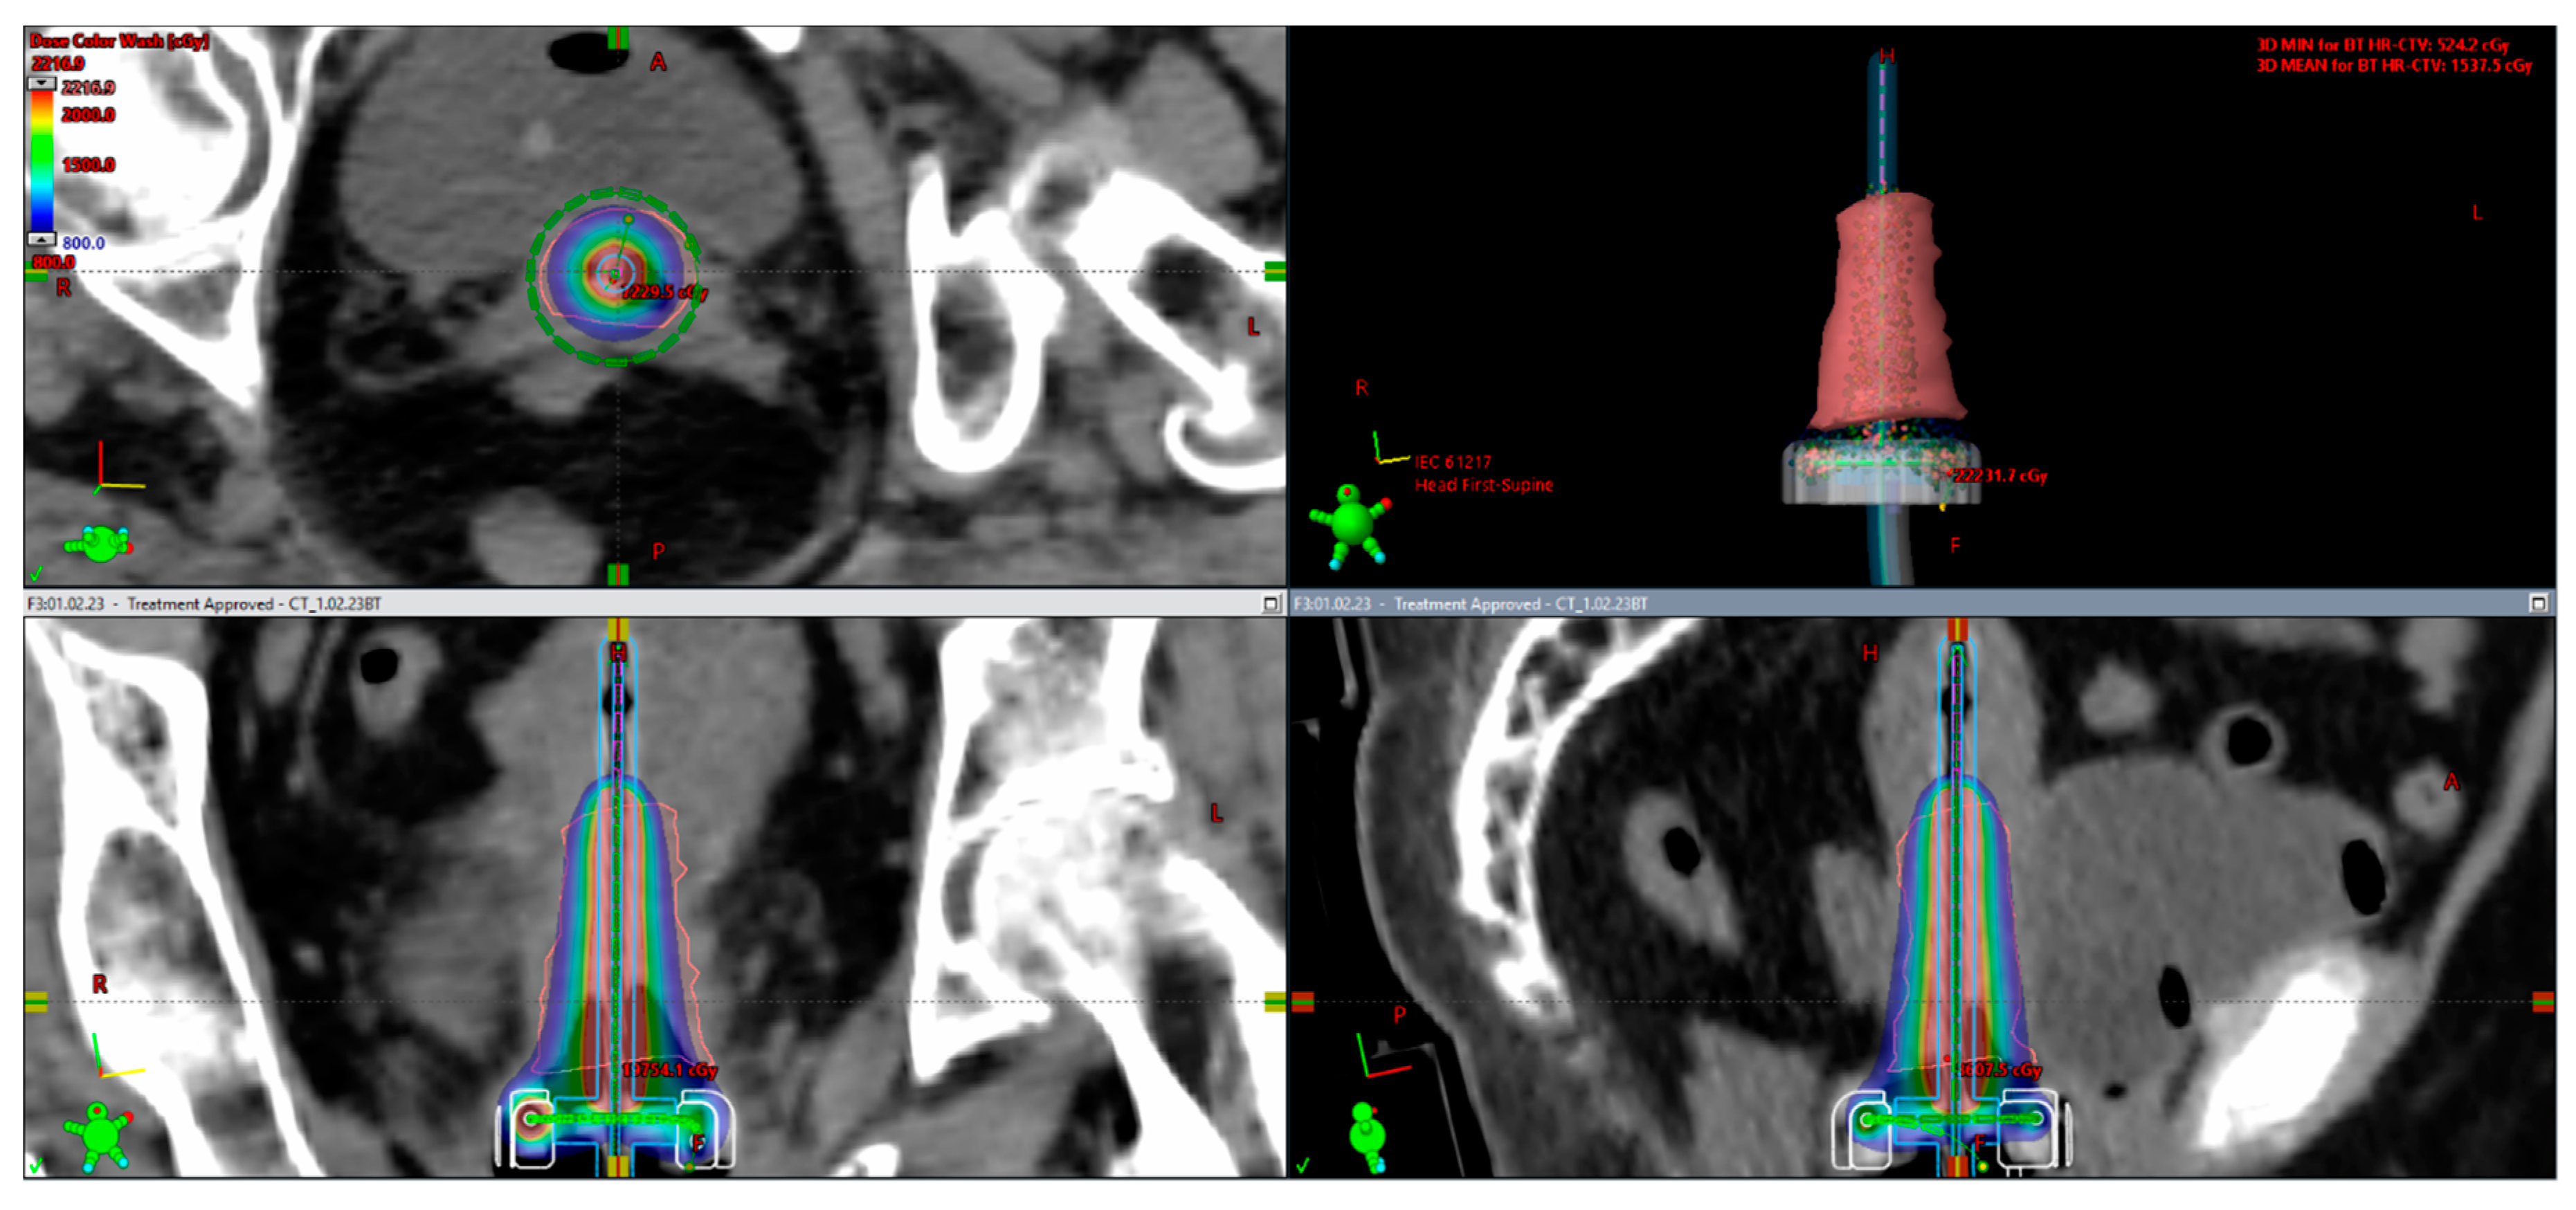

- Anghel, B. PO24: High Dose-Rate Tandem and Ovoid 3D CT Based Brachytherapy in Cervical Cancer: Initial Single Center Experience. Brachytherapy 2021, 20, S66–S67. [Google Scholar] [CrossRef]

- Charra-Brunaud, C.; Harter, V.; Delannes, M.; Haie-Meder, C.; Quetin, P.; Kerr, C.; Castelain, B.; Thomas, L.; Peiffert, D. Impact of 3D image-based PDR brachytherapy on outcome of patients treated for cervix carcinoma in France: Results of the French STIC prospective study. Radiother. Oncol. 2012, 102, 305–313. [Google Scholar] [CrossRef]